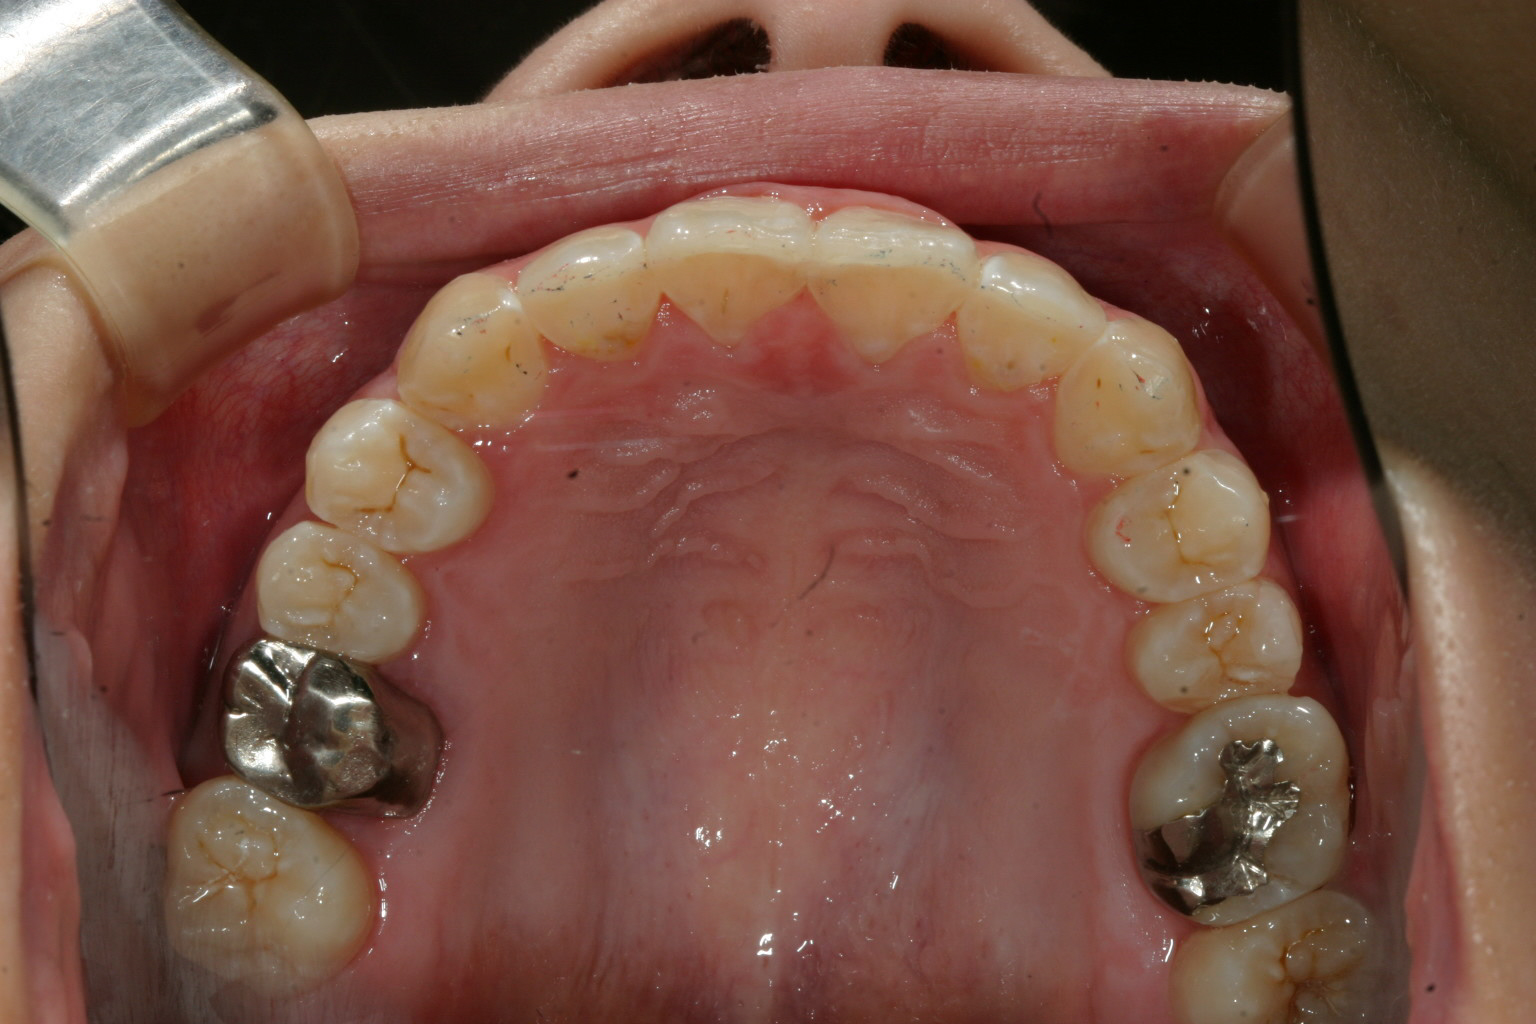

右の八重歯が飛び出してるのが気になりますね~

下の前歯もガタガタです。

抜歯無しでここまで改善致しました。

下顎のガタガタも綺麗になりました。

このケースは非抜歯で犬歯の唇側転移を改善致しました。

下顎も結構ガタガタしてましたが患者様の熱心な頑張りで僅か1年4カ月でこの様に綺麗に改善しました。